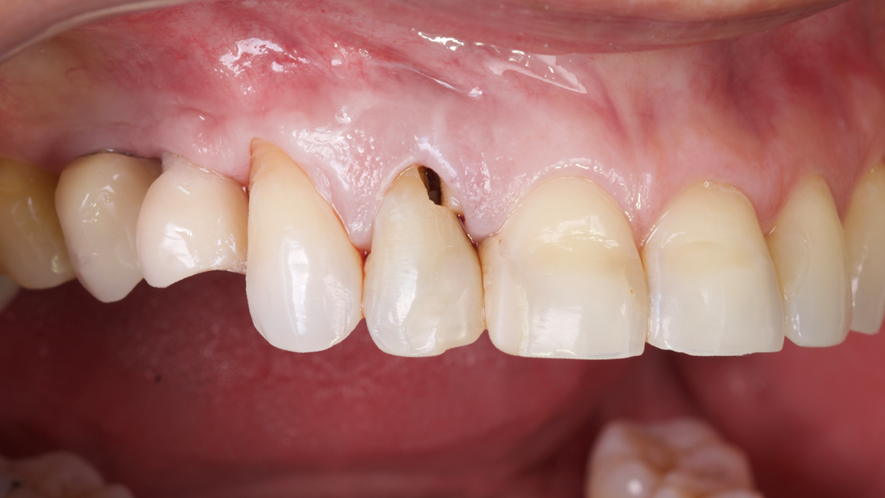

Este trabalho tem como objetivo relatar um caso clínico de exodontia minimamente invasiva de um incisivo lateral superior com fratura radicular, realizando implante imediato em alvéolo pós-extração, enxerto de tecido conjuntivo subepitelial e osso bovino liofilizado para preenchimento de GAP, prontamente à instalação de pilar reto e provisório imediato.